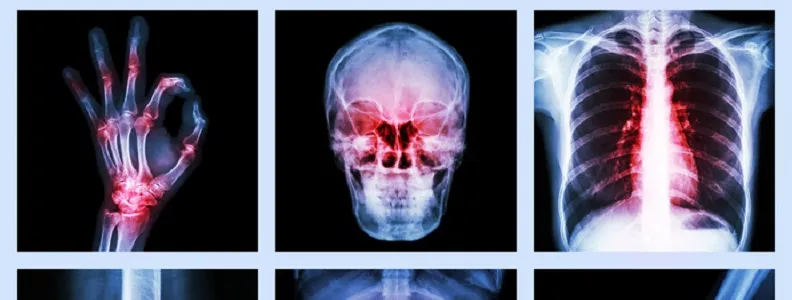

Niedobór witaminy K2 objawia się problemami z krzepnięciem, osłabieniem kości i zwapnieniem tętnic

- Wczesne objawy niedoboru obejmują zwiększoną skłonność do siniaków, krwawienia z nosa i dziąseł oraz dłuższe gojenie się ran.

- Długoterminowy deficyt prowadzi do osteoporozy, zwiększonego ryzyka złamań i zwapnienia tętnic, co zagraża sercu.

Z mojego doświadczenia wynika, że zrozumienie mechanizmów działania witaminy K2 jest fundamentalne dla docenienia jej znaczenia. Witamina K2 działa jak swoisty "dyrygent" dla wapnia w naszym ciele. Aktywuje ona dwa kluczowe białka: osteokalcynę, która transportuje wapń do kości i zębów, oraz białko MGP (Matrix Gla Protein), które zapobiega odkładaniu się wapnia w miejscach, gdzie jest on niepożądany czyli w naczyniach krwionośnych, chrząstkach i innych tkankach miękkich. Bez odpowiedniej ilości K2, wapń może gromadzić się w tętnicach, prowadząc do ich zwapnienia i usztywnienia. Oprócz tej kluczowej funkcji, witamina K2, podobnie jak K1, bierze udział w procesie krzepnięcia krwi, choć jest to jej mniej dominująca rola.

To jest chyba najbardziej podstępny i niebezpieczny skutek niedoboru witaminy K2. Mówię tu o kalcyfikacji, czyli zwapnieniu tętnic. Bez aktywnego białka MGP, które wiąże wapń w naczyniach krwionośnych i zapobiega jego odkładaniu, wapń zaczyna gromadzić się w ścianach tętnic. Powoduje to, że naczynia stają się sztywne, tracą elastyczność i są bardziej podatne na uszkodzenia. Ten proces jest kluczowym czynnikiem rozwoju miażdżycy, choroby wieńcowej, a także nadciśnienia. Zwapnienie tętnic to cichy zabójca, który przez lata nie daje żadnych objawów, a kiedy już się pojawią, często jest za późno. Dlatego profilaktyka poprzez odpowiednią podaż K2 jest tak ważna dla zdrowia serca i całego układu krążenia.